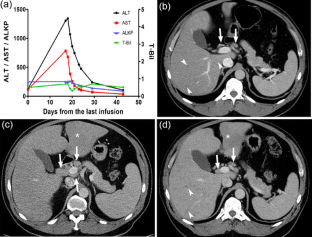

Ipilimumab is a novel immunomodulator demonstrating promising efficacy in treatment of melanoma and other cancers. The clinical benefit from ipilimumab can be hampered by the immure-related adverse events (irAEs) caused by dysregulation of host immune system. Ipilimumab associated hepatitis is also an important irAE, however, there have been limited descriptions of its clinicopathologic and imaging characteristics. We aim to describe the clinicopathologic and imaging characteristics of 6 patients who were diagnosed as ipilimumab associated hepatitis during the ipilimumab treatment for melanoma. The clinical features of these patients were as follows: (1) severe cases with systemic symptoms and highly increased level of liver function tests (LFTs), and (2) mild asymptomatic cases with mildly increased level of LFTs. In severe cases with ALT >1,000 IU/L, imaging findings were characterized by mild hepatomegaly, periportal edema, and periportal lymphadenopathy, while mild cases showed normal imaging findings. This spectrum of imaging findings in our series was similar to that of common causes of acute hepatitis. Among 3 cases with pathologic specimen, two cases showed severe panlobular hepatitis with prominent perivenular infiltrate with endothelialitis, suggestive of predominant injury to hepatocytes, while the other case showed mild portal mononuclear infiltrate around proliferated bile ductules, suggestive of predominant injury to bile ducts. In summary, ipilimumab associated hepatitis may demonstrate variable imaging findings according to its clinical severity, and histologically may manifest either as a predominant injury to hepatocytes (acute hepatitis pattern) or as a predominant injury to bile ducts (biliary pattern).

Fig. 1